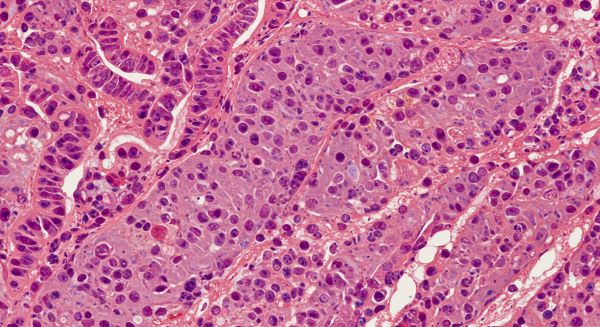

- 간 조직 생검: 필요 시 정밀 진단